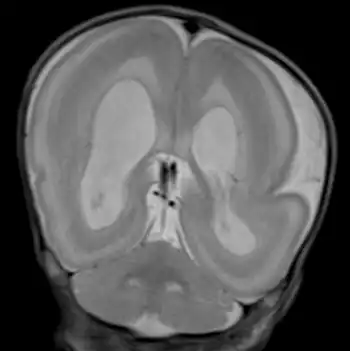

Visuals of the brain

The brain is usually grossly abnormal in outline when someone is diagnosed with Miller–Dieker syndrome. Only a few shallow sulci and shallow Sylvian fissures are seen; this takes on an hourglass or figure-8 appearance on the axial imaging. The thickness and measurement for a person without MDS is 3–4 mm. With MDS, a person's cortex is measured at 12–20 mm.